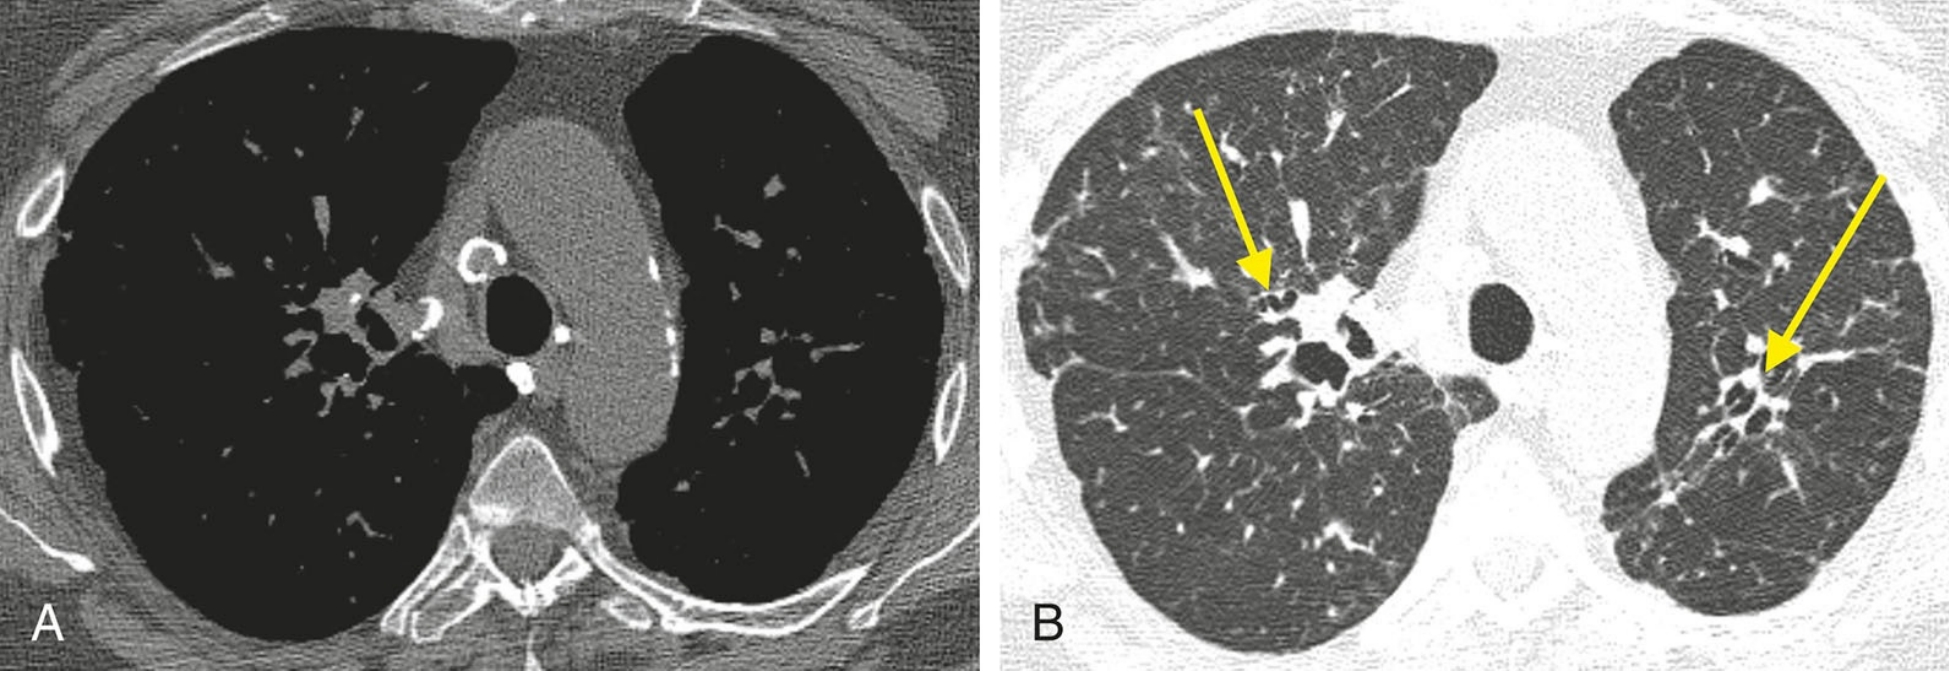

57a03c15e8d1b5dcc46ec6b10a3d6b28.jpg

典型结节病表现为支气管血管周围和胸膜下结节。本例为右肺上叶有局限性受累,支气管血管周围(红箭)和胸膜下(黄箭)可见多发结节。